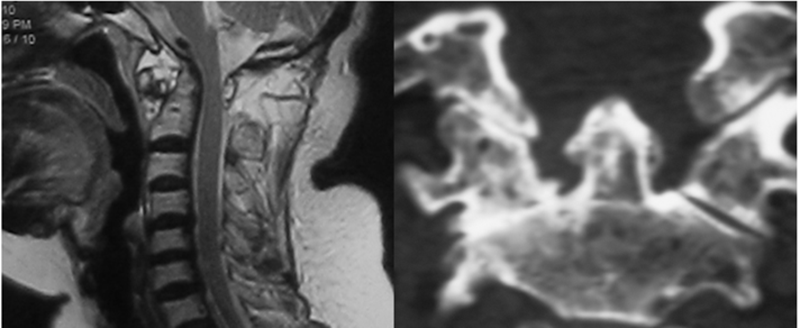

由于RA引起的血管翳“形成——破坏——再形成”的循环炎症反应,会导致这些韧带松弛,甚至产生破坏,从而出现C1-C2之间不稳。MRI检查可在T2加权像发现齿突周围混杂的高信号,CT有时可以发现齿突骨质的破坏及关节突关节病理性改变。

MRI显示齿突前缘混杂信号,CT显示齿突骨质破坏及一侧关节突关节已经融合